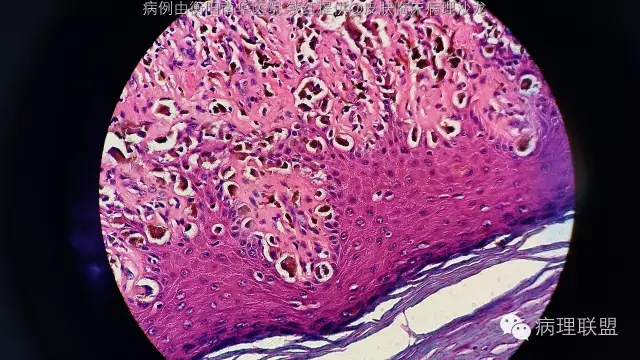

诊断依据,1,临床特点,常发生于老年人,足底,皮疹大于6mm,边缘不规则,色沉不均。2,鳞状上皮上皮脚延长,异型色素细胞沿上皮脚两侧基底层呈连续性增生。3,真皮乳头见灶性异型色素细胞浸润。

这张最明显,异型色素细胞沿上皮脚两侧,基底层呈连续增生

这张图尤其左下方显示真皮乳头层及真皮浅层有灶性异型色素细胞浸润